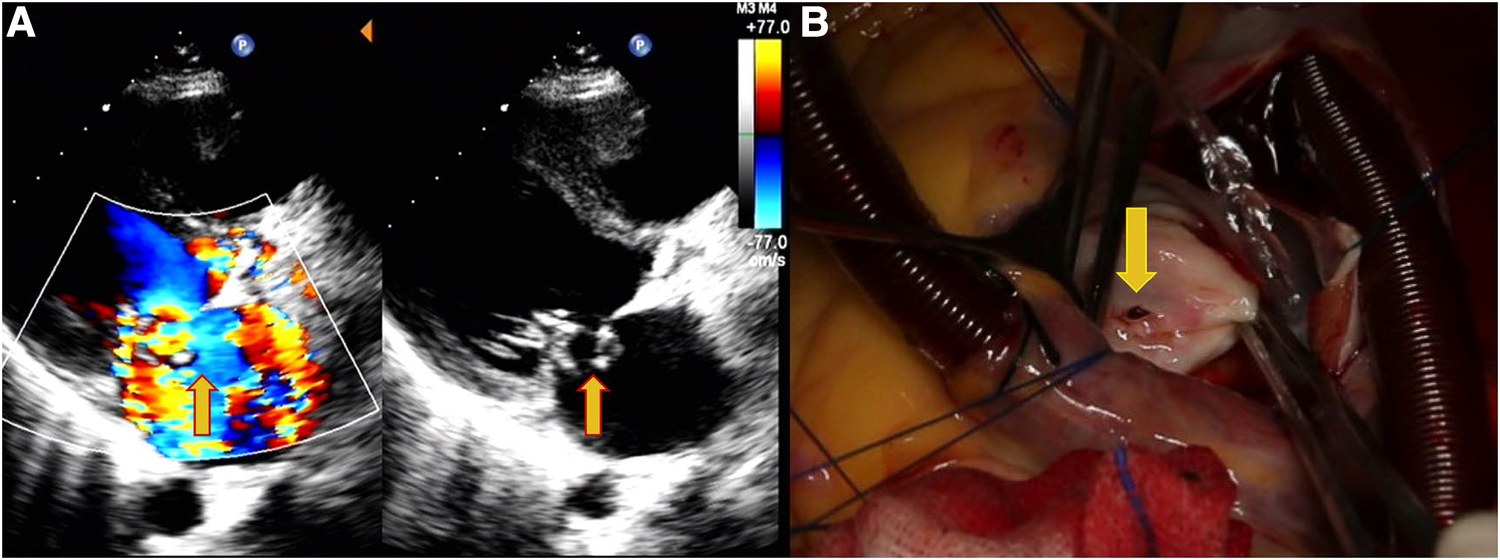

Figure 1

Echocardiography data of a 31-year-old female patient with shortness of breath, palpitations, and fever for 7 days. (A) Perforation of the MVA and regurgitation (yellow arrows). (B) Site of the MVA perforation during surgery (yellow arrows).